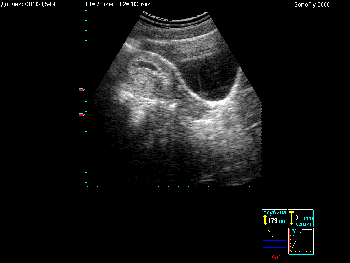

Примеры того, как выглядит экран при различных режимах сканирования можно увидеть в Таблице 4.

Таблица 4. Общий вид экрана в различных режимах сканирования.

| Вид экрана | Режим сканирования |

|---|---|

![]() |

Режим В+В |